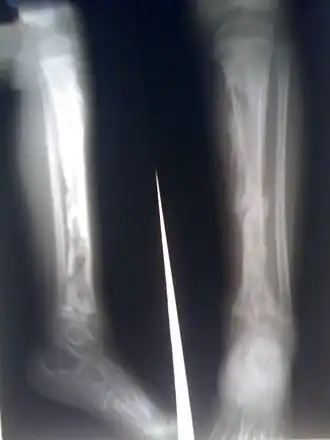

Ostéomyélite du tibia d'un jeune enfant. Les nombreuses zones radio-transparentes correspondent à des abcès dans l'os.

Bilan radiographique

Les radiographies standard de face, profil complété par des clichés comparatifs et de 3/4 en cas de doute sur une lésion. Au stade du début, on recherche un flou des parties molles adjacentes à la métaphyse. À la phase d'état, on recherche une apposition de fines lamelles osseuses à la corticale métaphysaire correspondant à la réaction périostée. Plus tardivement apparaissent :

• des lacunes métaphysaires ;

• des irrégularités des corticales ;

• des séquestres osseux (fragment osseux d'aspect dense libre et irrégulier).